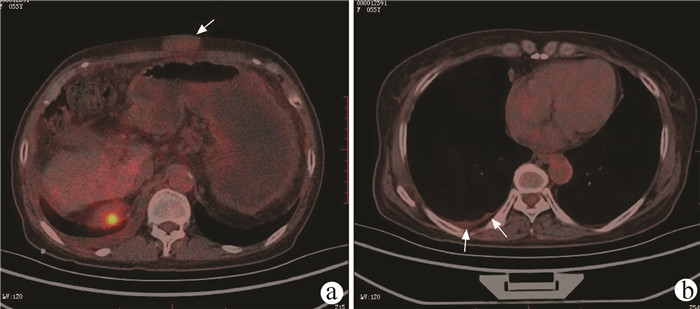

经正中裂联合左右侧入路完整切除肝尾状叶治疗小儿肝泡型包虫病1例报告

李汗, 侯立朝, 王海久, 王聪, 樊海宁

2022, 38(2): 426-429. DOI: 10.3969/j.issn.1001-5256.2022.02.033

摘要(1147) HTML (290) PDF (3527KB)(48)

摘要: